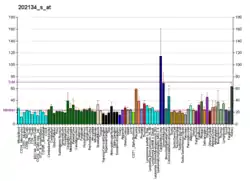

Cancers

WWTR1 (TAZ) is implicated a wide variety of cancers including melanoma, head and neck squamous cell carcinoma, breast cancer, non-small cell lung cancer, and others due to its high gene and histological expression, as well as correlation with increased metastasis and poorer survival in animal studies and patient data.[9] Along with the structurally similar co-regulator YAP, many studies have described their role in promoting oncogenesis, altering neoplastic metabolism, and generating resistance to therapeutic intervention.[8][9][32][33] In particular, TAZ overexpression conferred resistance to cisplatin chemotherapy as well as immunotherapy treatment with a PD-1 antibody.[32]